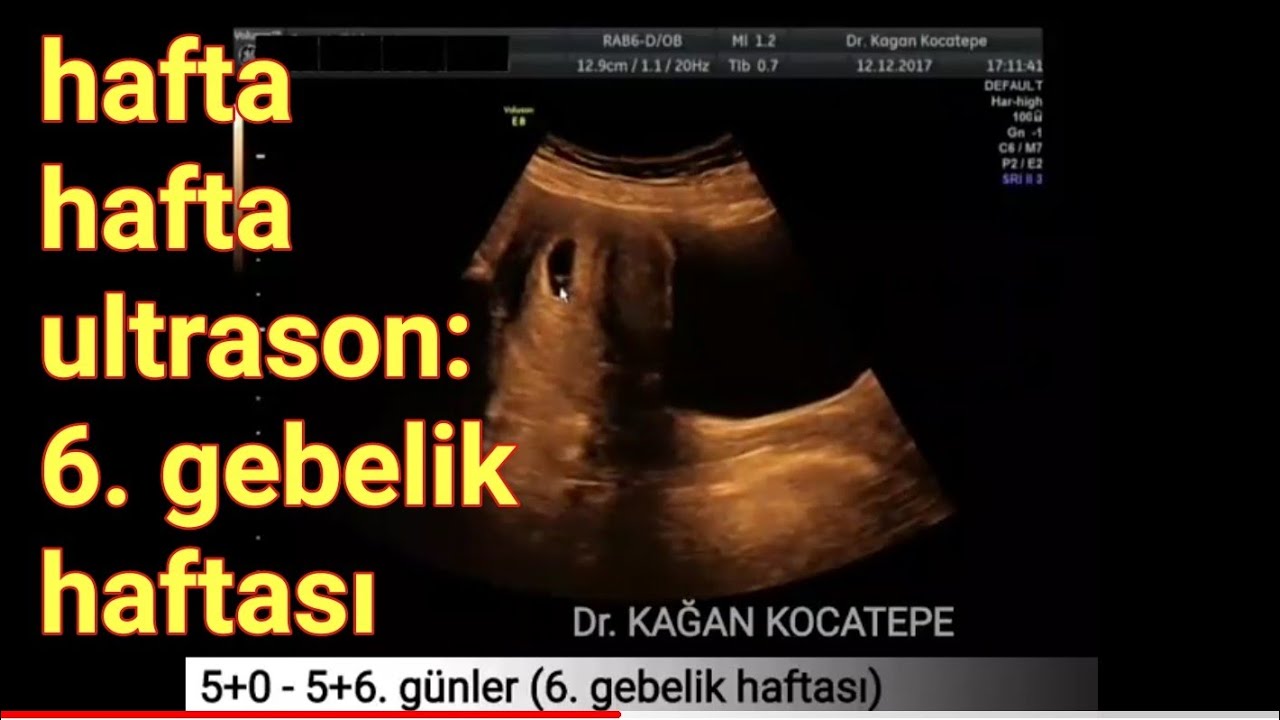

6. gebelik haftasında anne karnındaki bebek açıklamalı